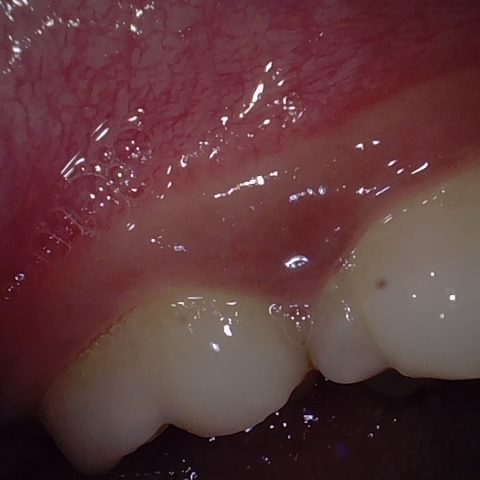

Image 6 / 400

NHD25466

Annotated as "Good"

Original Image Rendering Image